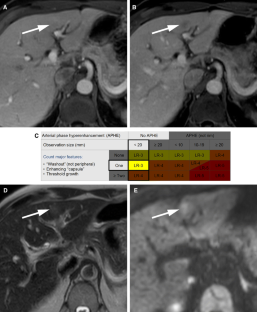

LI-RADS® algorithm: CT and MRI

The Liver Imaging Reporting and Data System (LI-RADS®) is an imaging-based diagnostic system applicable in patients at high risk of hepatocellular carcinoma (HCC). In LI-RADS, each liver observation is assigned a category that reflects probability of benignity, HCC, or other malignancy. Familiarity with the LI-RADS diagnostic algorithm is necessary to appropriately implement LI-RADS in clinical practice. This review discusses steps necessary for application of the LI-RADS algorithm and provides examples illustrating each step.